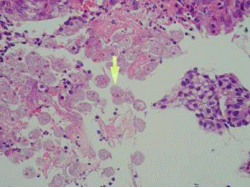

1. 塗抹検査(グラム染色・抗酸菌染色)

検査材料を染色し、顕微鏡にて観察します。原因となる細菌や真菌(写真参照)を推定します。

2. 培養・同定検査

培養検査は、培地に検査材料を塗り、肉眼で菌を観察できる状態にします。

同定検査は、発育してきた菌(写真参照)の性状を調べ、菌名を決定します。